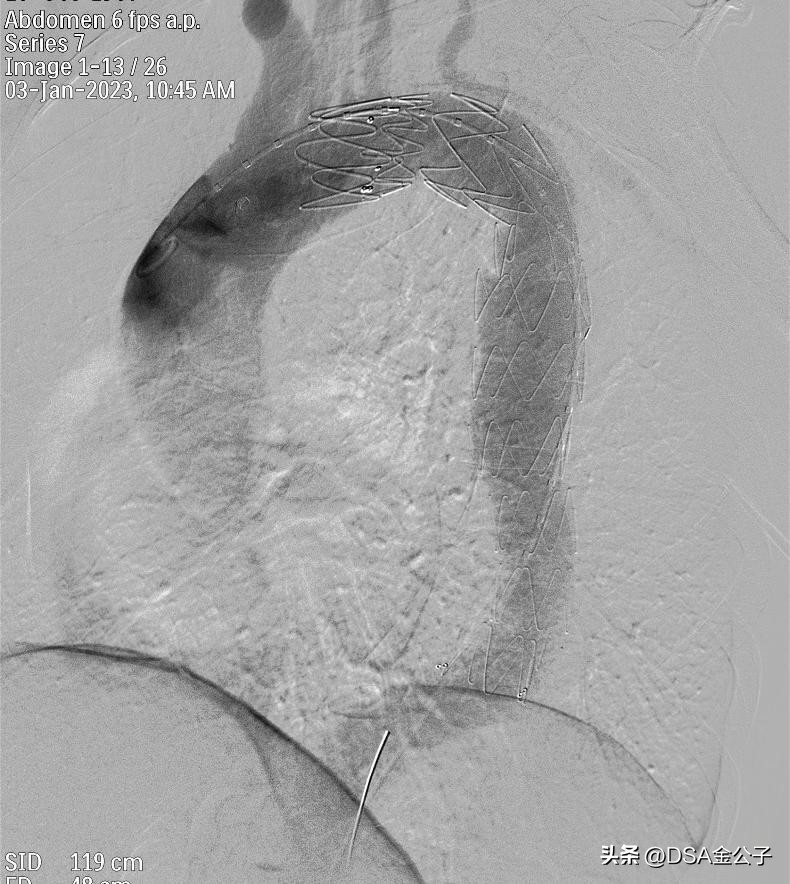

植入支架后,动脉瘤消失